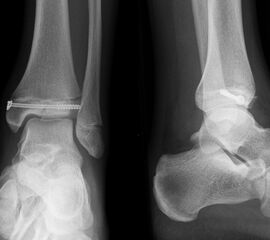

Fugengelenkfrakturen treten typischerweise vor dem 10. Lebensjahr auf, in einer Phase, in welcher die Wachstumsfugen noch weit offen sind. Dieser Frakturtyp betrifft fast ausschließlich den medialen Malleolus. Laterale Frakturen sind extrem selten, teilweise kommt es zu lateralen Bandverletzungen oder Fugenschaftfrakturen der distalen Fibula. Die Frakturlinie verläuft in einer Verlängerungslinie von der medialen Taluskante nach proximal. Häufig stellen sich Verletzungen des Innenknöchels im Röntgenbild schlechter dar, insbesondere wenn die Aufnahmen verdreht sind oder die Ebene der Fraktur bei geringer Dislokation verkippt zur Röntgenebene liegt. Besteht klinisch der geringste Hinweis auf eine Verletzung des Innenknöchels, muss aufgrund der Tragweite der Verletzung durch entsprechende Aufnahmen gegebenenfalls auch Schnittbildverfahren die Verletzung sicher diagnostiziert oder ausgeschlossen werden (Abb. 15).

„Kadiläsion“- Mediale Malleolarfraktur

Bei kindlichen Verletzungen des medialen Malleolus handelt es sich nach L. v. Laer um eine sogenannte Kadiläsion, d.h. eine Verletzung mit hohem Risiko eines schlechten Behandlungsergebnisses bei nicht korrekter Behandlung. Selbst bei optimaler Therapie ist das Risiko für spätere Wachstumsstörungen hoch, sodass diese Verletzungen nicht selten ein juristisches Nachspiel haben. Durch die Verletzung der wachstumsaktiven Zone kann es zu einem vorzeitigen Verschluss der Wachstumsfuge kommen, mit entsprechendem Fehlwachstum. Das Risiko eines vorzeitigen Verschlusses der Wachstumsfuge korreliert mit dem Ausmaß der Schädigung der wachstumsaktiven Zone. Ab dem 13. Lebensjahr wird das Risiko bei reduzierter Wachstumsaktivität zunehmend geringer.

Fugengelenkfrakturen können die Wachstumsfuge durchkreuzen (Abbildung 16a), ohne oder nur mit minimaler Beteiligung der Fuge sehr weit medial liegen (Abbildung 16b) oder durch die Fuge auslaufen (Abbildung 16c). Relevant für die Wachstumsprognose ist weniger die Form der Fraktur, sondern das Alter des Patienten zum Zeitpunkt des Traumas sowie das Ausmaß der Schädigung der Wachstumsfuge, wobei eine Korrelation mit dem Ausmaß der Dislokation besteht.

THERAPIE

Behandlungsziel ist die exakte Rekonstruktion der Gelenkfläche sowie die Minimierung des Risikos einer späteren Wachstumsstörung. Dislozierte Frakturen werden offen reponiert, die Osteosynthese erfolgt mit einer Kleinfragmentschraube. Finden sich viele kleine Fragmente kann eine K-Draht Osteosynthese durchgeführt werden. Wird der Innenknöchel operiert, kann bei gleichzeitiger hochgradiger lateraler Instabilität eine Rekonstruktion des lateralen Bandapparats durchgeführt werden. Fibula Frakturen stellen sich meist spontan ein, sodass hier keine zusätzliche Osteosynthese notwendig ist.